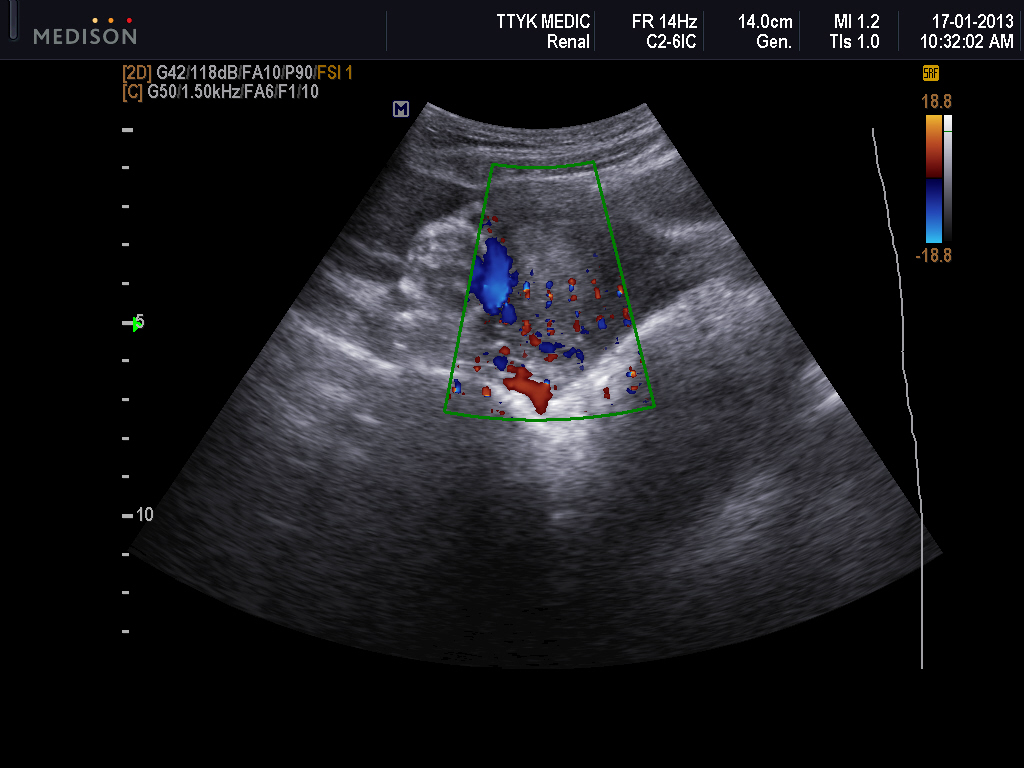

Bệnh nhân nữ 30 tuổi, PARA 1011, tiền sử mổ TNTC ở vòi tử cung bên phải; kinh nguyệt đều, vòng kinh 30 ngày. Bệnh nhân bị chậm kinh một tháng, đau âm ỉ hạ sườn phải 1 tháng, không ra máu âm đạo. Bệnh viện Phụ Sản Hà Nội nghi u nguyên bào nuôi và chuyển đến Bệnh viện Phụ Sản Trung ương. Xét nghiệm β-hCG: 73.047 IU/L; siêu âm Doppler: dưới gan có hình ảnh túi thai d=35mm, chiều dài phôi: 22mm, tim thai (+). Chẩn đoán thai dưới gan. Nội soi: khối thai 3cm nằm ở cạnh phải túi mật, gần tĩnh mạch cửa. Bóc khối thai và cầm máu bằng dao điện và chèn Spongel. Xét nghiệm β-hCG sau 72 giờ: 14.109 IU/L. Giải phẫu bệnh: gai nhau điển hình.

| Hình 3. Hình ảnh siêu âm của bệnh án 2 |